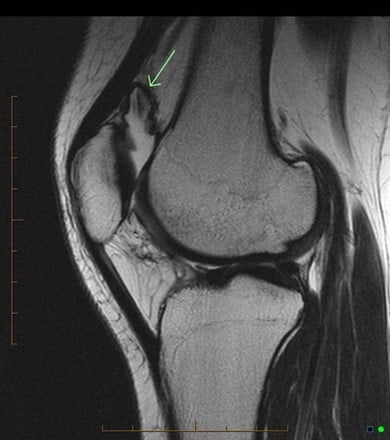

This is an MRI diagnosis and is best appreciated with the full set of images

Case courtesy of Dr. Andrew Dixon, Radiopaedia.org. From the case rID: 41239